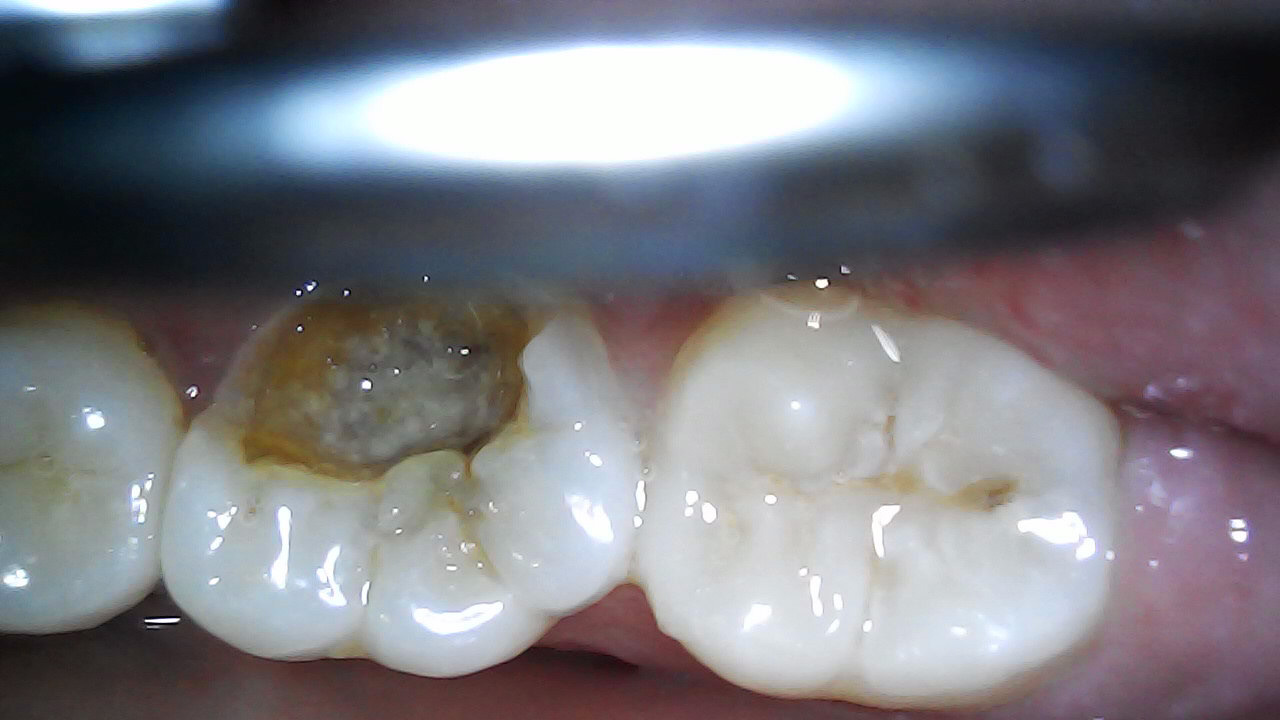

16 Pre-op

Initial